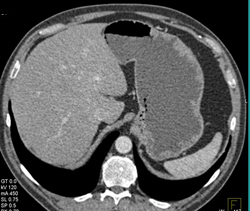

1 Cm GIST Tumor